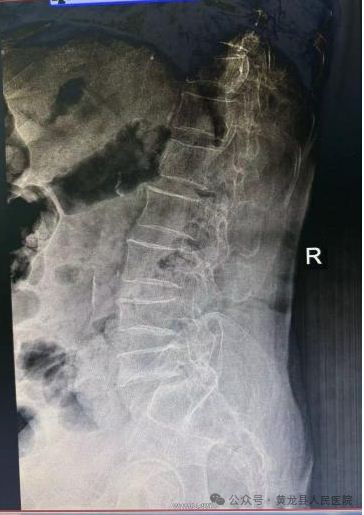

术前术后X线影像

患者女,88岁,因病理性骨质疏松导致胸腰背部疼痛,翻身、弯腰、下地活动严重受限。入院后行X线检查示:胸椎体压缩性骨折(胸11)。

术中最大限度保留了腰背肌肉的完整性,减少患者术后疼痛、手术出血和切口感染等手术并发症,同时大大缩短了患者康复时间。术后第1天,患者胸腰部疼痛显著缓解,不仅能自行完成床上翻身活动还可以下地活动,达到预期效果,术后第2天出院,恢复生活自理能力。患者及家属对手术治疗效果非常满意,向方继荣主任及外科全体医护人员多次表示感谢,出院后特送来锦旗一面再次表示感谢。